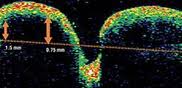

La OCT podría proporcionar una evaluación objetiva confiable de los cambios en la capa de fibras nerviosas de la retina (CFNR). También se aprecian cambios en los PEV y en la ecografía.